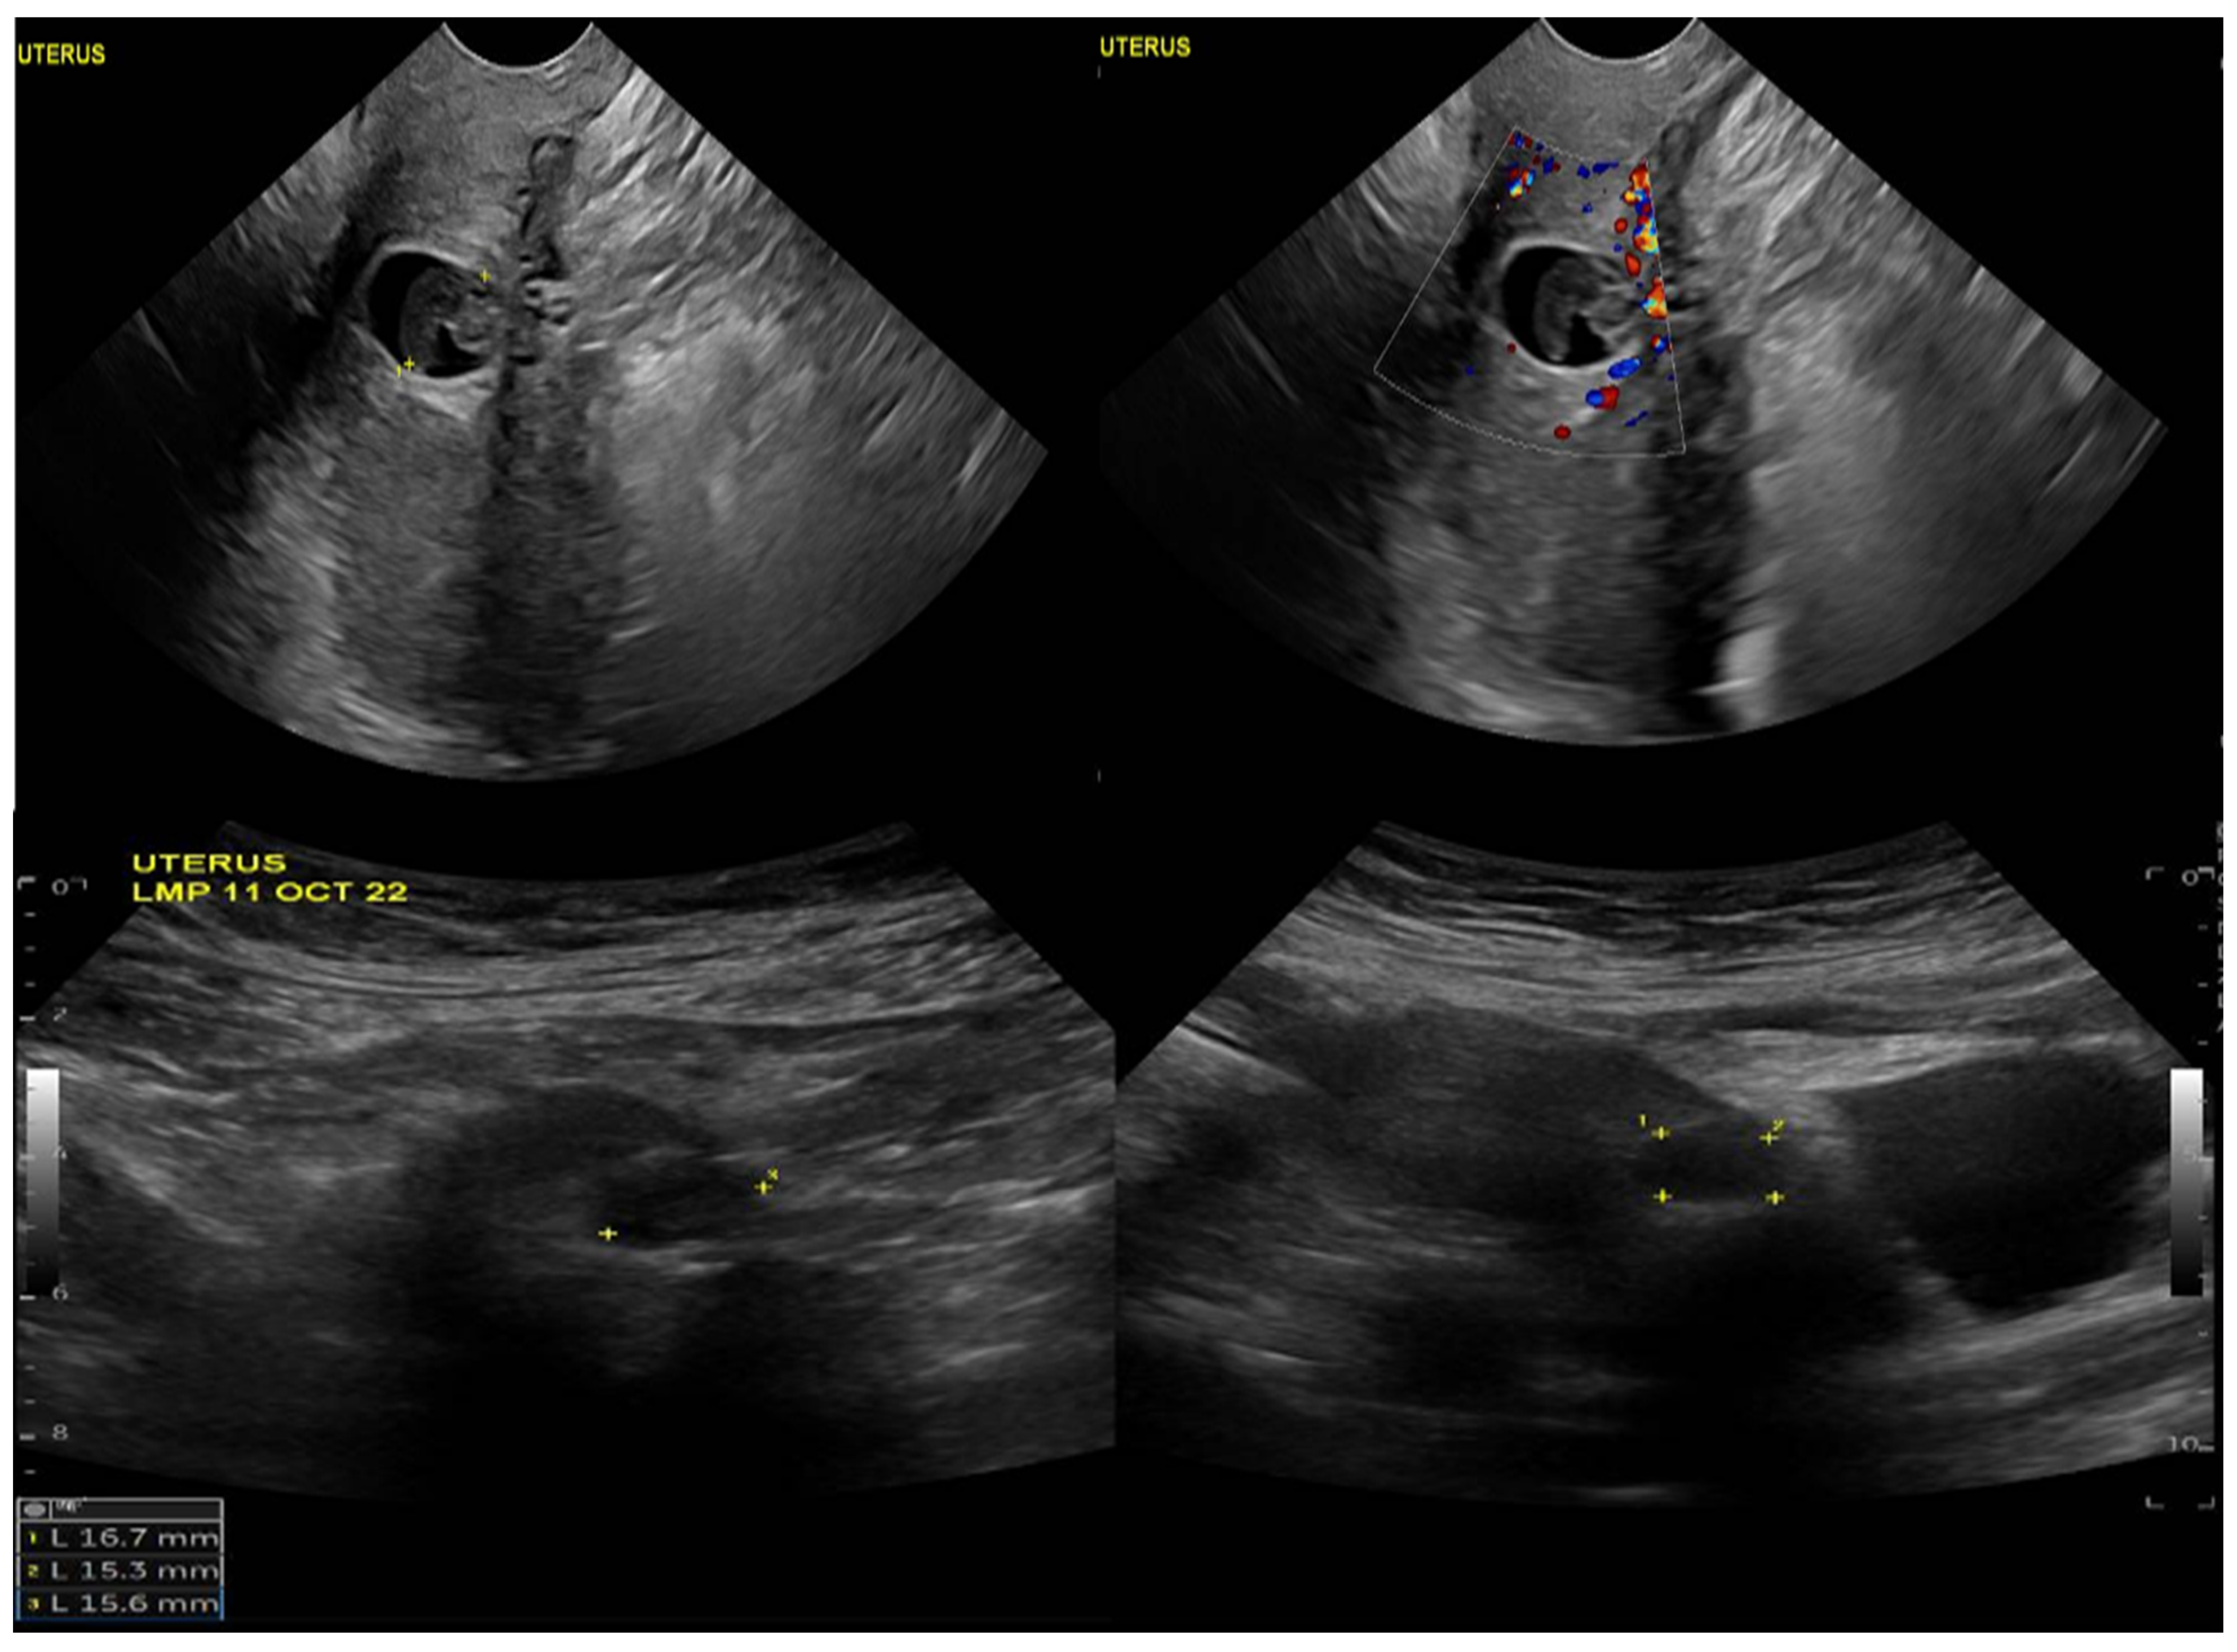

Upon physical examination, the patient was vitally stable with no active bleeding. A speculum examination showed a healthy-looking vulva and vagina, no bleeding, and a closed cervical os. The patient’s B-HCG level was 6878 mIU/mL, which increased to 9355 mIU/mL when repeated. A transvaginal ultrasound showed an average-sized uterus measuring 8 × 4 cm, a homogenous myometrium, and an endometrium measuring 4 mm with no definite endometrial gestational sac (Figure 1). The ultrasound also revealed a well-defined ectopic gestational sac showing a fetal pool with no definite pulsations in the anterior wall of the lower uterine segment at the assumed region of the previous scar.

Figure 1.

Ultrasound image of the uterus, demonstrating a well-defined ectopic gestational sac and showing a fetal pool with no definite pulsations in the anterior wall of the lower uterine segment at the assumed region of the previous scar.